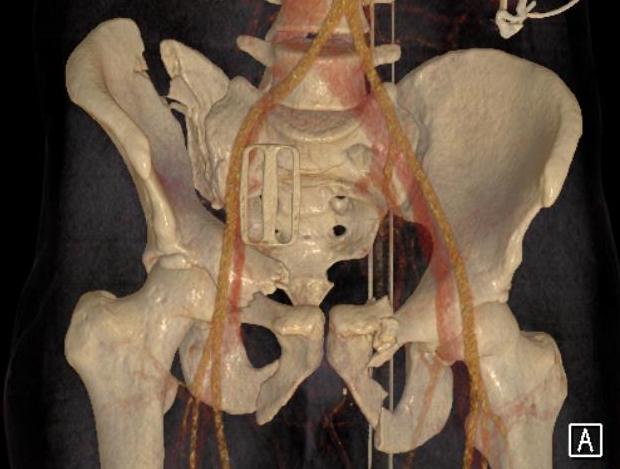

Lumbosacral fixation with SI screw - triangular osteosynthesis

Sacral plate, sacroiliac screws, ramus screws

Posterior stabilisation critical

- sacro-iliac screws

- lumbosacral fixation